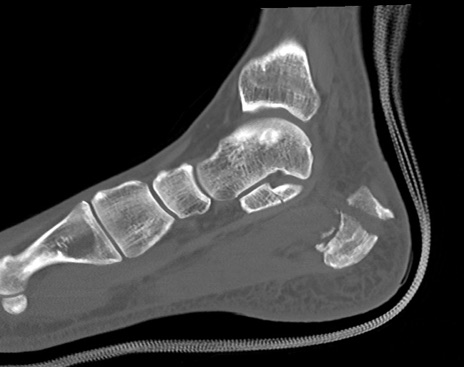

症例37 左足関節CT(矢状断像)

左足関節CT

冠状断像